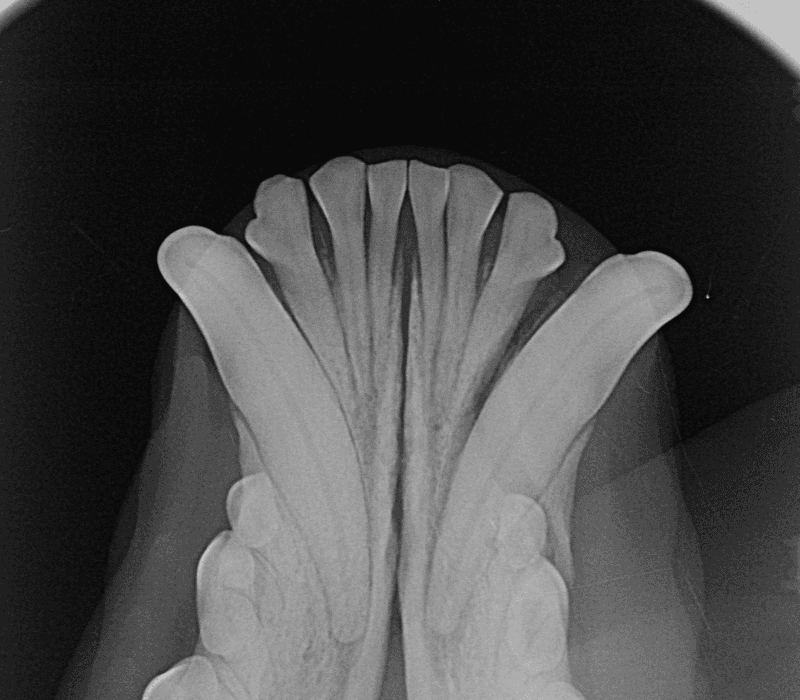

Die unter Sedierung angefertigten Röntgenaufnahmen bestätigten die vollständige Avulsion sowie eine begleitende Alveolarfraktur. Da das Desmodont (Parodontalligament) als vital beurteilt wurde, bestand eine klare Indikation zur Replantation dieses funktionell relevanten Arbeitszahns.

Die Repositionierung in die frakturierte Alveole erfolgte unter Allgemeinanästhesie, gefolgt von einer adhäsiven Schienung mittels Acrylharz an die benachbarten Zähne. Die klinische Rationale war eindeutig: Unmittelbare Stabilisierung zur Förderung der parodontalen Revaskularisation und der ossären Heilung. Die postoperativen Anweisungen umfassten ausschliesslich Weichkost, den strikten Verzicht auf Kauobjekte sowie wöchentliche klinische Kontrollen.